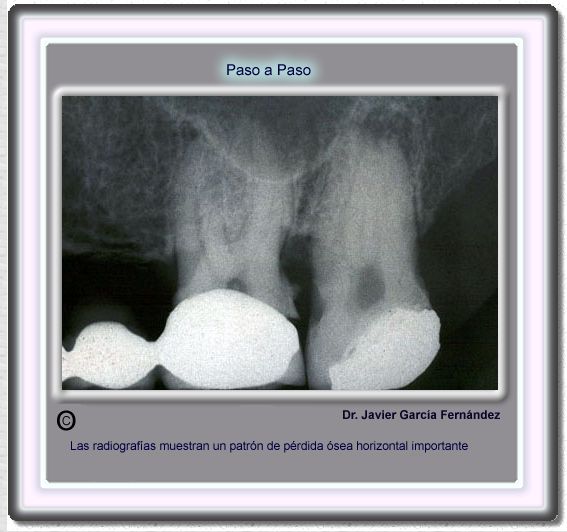

image 137